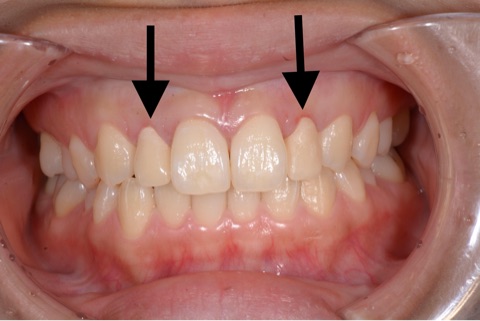

矯正歯科